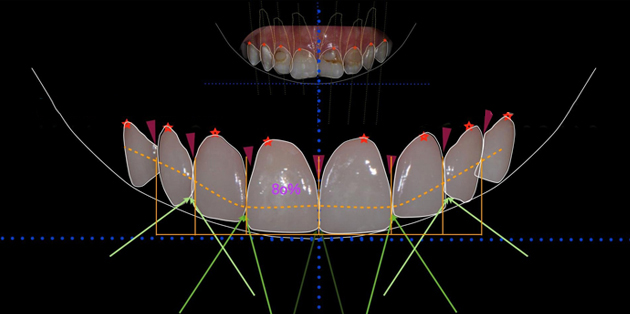

1数字化微笑分析

确定前牙牙龈缘高度、长宽比例、大小比例,绘制牙齿形态,完成DSD设计